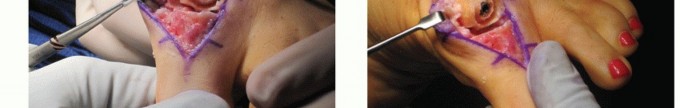

Postoperative Care

A compressive dressing is placed intraoperatively.

The dressing is changed at 2 to 3 days postoperatively for a light dressing along the dorsal incision only with a waterproof

OpSite (FIG 8). This allows for less restriction due to the bandage and encourages early range of motion.

Early range-of-motion exercises are emphasized in an effort to preserve the motion gained intraoperatively. Some degree of motion loss is anticipated postoperatively from its intraoperative measurements, although every effort is made to minimize this amount.

FIG 8 • The initial dressing is changed to a light dorsal postoperative dressing so as not to restrict early motion. A waterproof sealed OpSite is used.*